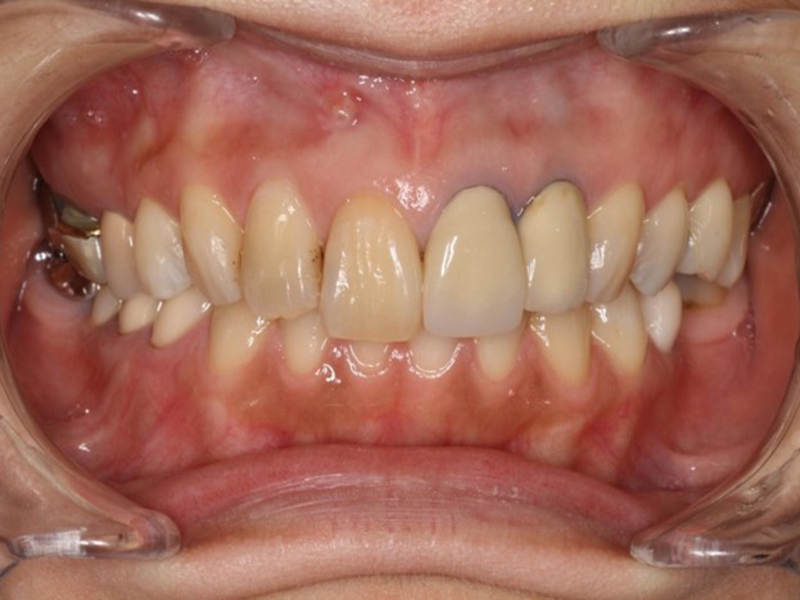

▼ ケース7 矯正終了→ホワイトニング→オールセラミックスによる修復

before

経過

after